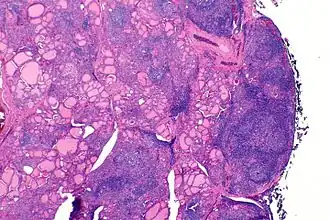

Coupe histologique d'une thyroïde atteinte par la maladie en coloration hématoxyline-éosine, montrant l'infiltration lymphoïde avec notamment la présence de follicules.

Sur le plan physiopathologique, les anticorps dirigés contre la thyroperoxydase et/ou la thyroglobuline causent une destruction progressive des follicules thyroïdiens de la glande thyroïde.

Macroscopiquement, le goitre est symétrique, non adhérent aux éléments péri-thyroïdiens et présente une surface capsulaire discrètement bosselée[1].

En microscopie les lésions consistent en une association de fibrose interstitielle, d'infiltration lymphoïde et de destruction épithéliale[1],[2]. Le degré de fibrose est très variable[1]. L'infiltration lymphoïde présente une organisation en follicules avec des lymphocytes B au centre et des lymphocytes T dans le cortex[2]. Les cellules épithéliales thyroïdiennes sont également modifiées, apparaissant élargies et acidophiles (cellules de Hürthle)[2].